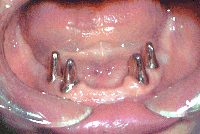

Teeth prepared for an overdenture - The denture will fit over the metal-covered teeth that have been

shaped by the dentist.